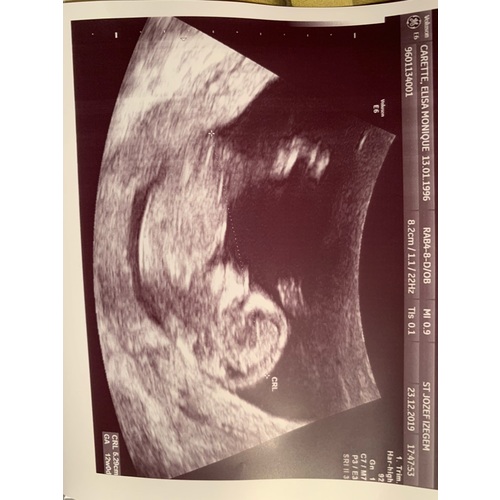

Reactie op Pippa96

Wie wil een gokje wagen? Jongen of meisje 馃檴馃檴

Girl. En ze lijkt een beetje boos te kijken hehe